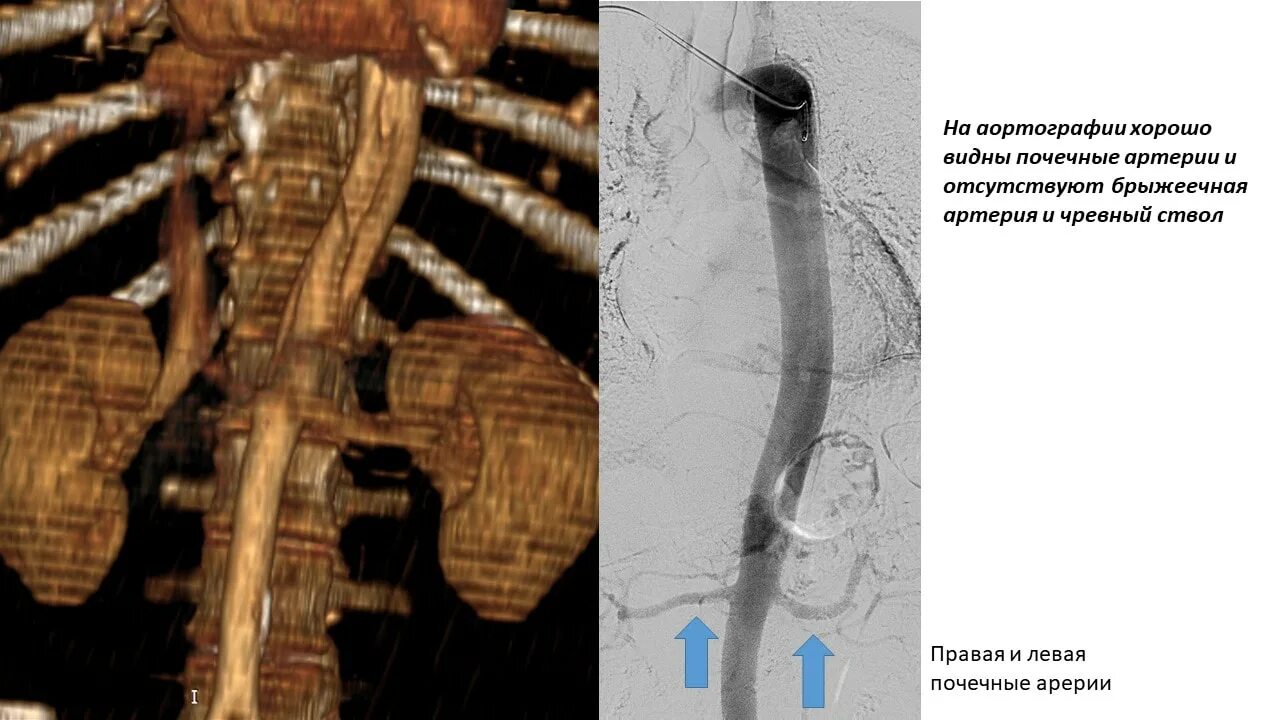

Тромбоз брыжеечной артерии